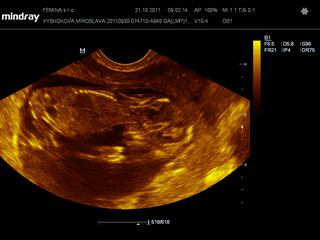

@kaekole zatial som bola len na tom vaginalnom sone. dnes mi robil, dnes som v 12+1, potom mi robil pred tyzdnom a potom este v 9+1.

ale dnes mi meral aj NT - ako si mi raz pisala, dokladne malicke prezrel + este mi povedal, ze ak chcem mat 100% istotu, aby som isla do Martina k jednemu specialistovi - MUDr. Frantisek Grochal

@lenkalela ja som citala, ze do 3 mm je to uplne v poriadku, tak sa nicoho neboj

tu je foto z dnesnej poradne 🙂